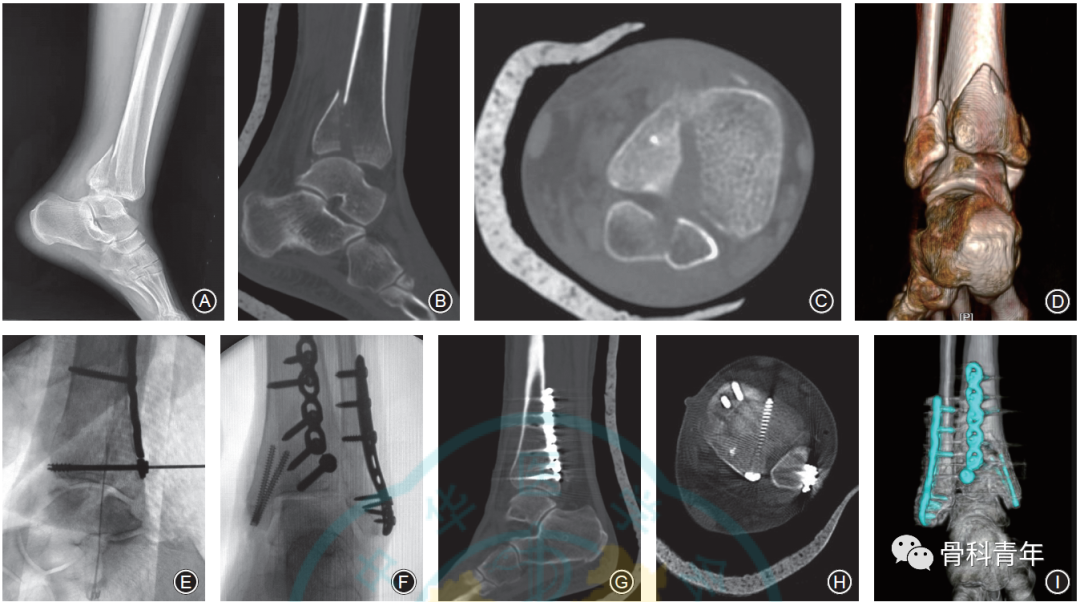

病例1: